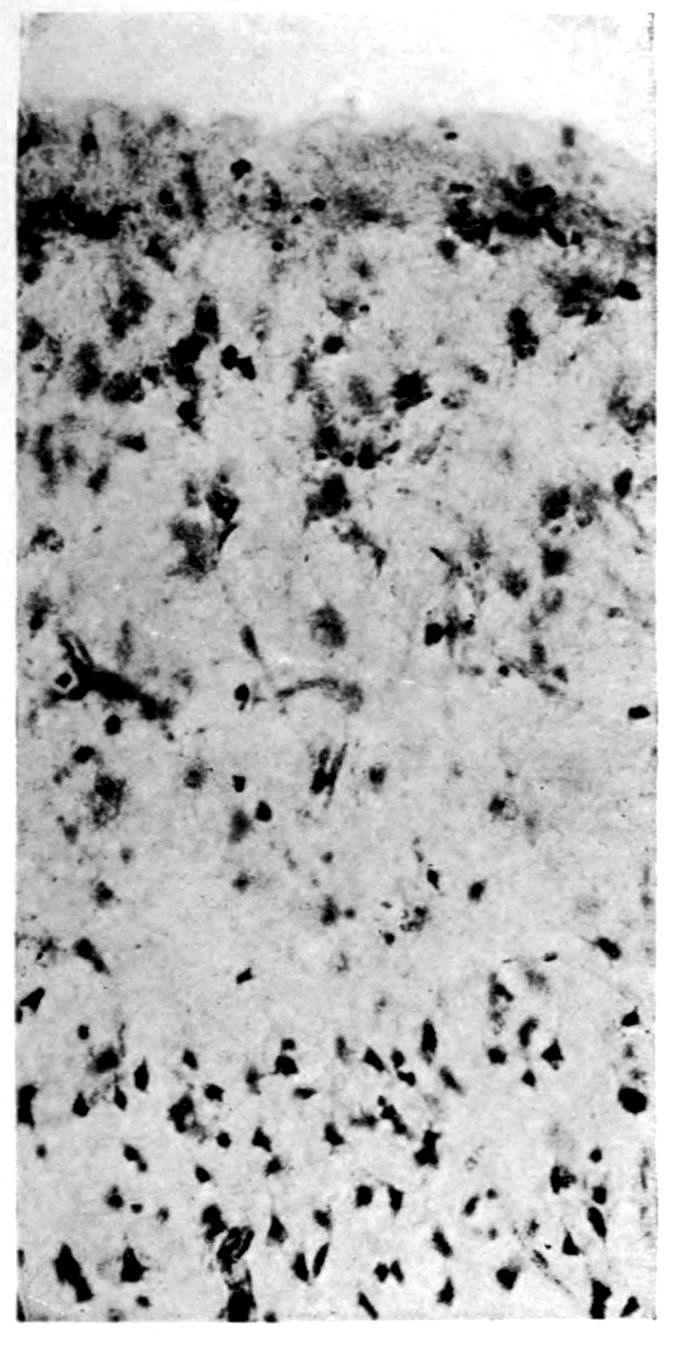

Apparent new formation of small blood vessel. Photographed by Dr. A. M. Barrett.

Rod cells (Stäbchenzellen) in paretic neurosyphilis. Photographed by Dr. A. M. Barrett.

Granular ependymitis—microscopic appearance of a marked example of “sanding” of ventricle.

41Characteristic and constant in paretic neurosyphilis is the Plasmocytosis and Lymphocytosis, Perivascular in distribution about small cortical vessels. There is also a characteristic (though characteristically less prominent) Plasmocytosis and Lymphocytosis, Meningeal in distribution. The pleocytosis of the spinal fluid, almost constant though variable in amount in life, is an indicator of the meningeal picture and less directly of the parenchymatous picture.

Granular Ependymitis (“sanding” of ventricle floors) is characteristic and may be regarded as part of the parenchymatous picture. This ependymitis is an indicator how chemical changes could be readily produced at least in the ventricular fluids, since the limiting membranes of the nerve tissue are here subject to multiple breaks. The “sanding” is a neuroglia reaction to these multiple small breaks (Weigert’s explanation).

Parenchymatous losses have led to Atrophy and Sclerosis, of very varying extent in different parts of the encephalon. The atrophy is characteristic in paretic neurosyphilis, but by no means constant. Numerous cases have come to autopsy without clearly defined gross atrophy. Sclerosis is also characteristic and even more frequent than atrophy, doubtless because sclerosis represents an earlier phase of a process eventuating in gross atrophy.